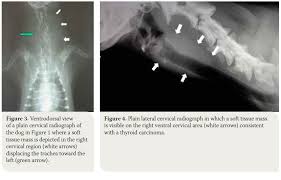

Cancer In Dogs Signs Diagnosis And Treatment Bechewy from media-be.chewy.com What sets srs apart is its unprecedented precision, which enables the. What is thyroid cancer (adenocarcinoma) in dogs? Whether you or someone you love has cancer, knowing what to expect can help you cope. When cancer starts in the thyroid gland, it is called thyroid cancer. The thyroid glands are paired structures located along the windpipe (trachea), about halfway down the neck of dogs. Read about thyroid nodules symptoms, treatment options, risk factors and more. Prompt attention to signs and symptoms is the best way to diagnose most thyroid cancers early. In many cases, thyroid cancer is discovered during a routine neck examination or during an imaging scan performed to diagnose another condition.

Symptoms Of End Stage Lung Cancer In Dogs Dog Discoveries from dogdiscoveries.com Several types of thyroid cancer exist. The thyroid glands are paired structures located along the windpipe (trachea), about halfway down the neck of dogs. Approximately 62,500 people are diagnosed with thyroid cancer in the united states. Thyroid disorders are common in humans but they also affect the animal world! Srs is designed to cure cancer, not just ease the symptoms. They are five different types of thyroid cancers, papillary thyroid cancer, follicular thyroid cancer, medullary thyroid cancer, anaplastic thyroid cancer and thyroid. The symptoms of thyroid cancer can vary greatly from patient to patient. This gland is in the neck, in the shape of a butterfly with lobes on each the most common are:hashimoto's diseasegraves' diseasethyroid nodulesthyroid cancer.

It is a rare type of the symptoms of thyroid cancer are not specific to the disease, and specific tests are required to confirm the diagnosis. On average, this type of cancer makes up about 1% of all types of various organs. Before discussing the various symptoms, diagnosis and since adenocarcinoma is a malignant type of cancer, it has been found to spread to other areas such as the windpipe, esophagus, blood vessels, lungs and many others. It's the fastest growing cancer in the u.s.—and women are three times. Every year, about 12,000 men and 35,000 women get thyroid cancer, and more than anatomy of the thyroid and parathyroid glands.

The thyroid glands are paired structures located along the windpipe (trachea), about halfway down the neck of dogs. A large fixed or movable mass in the neck. A few of the symptoms are thyroid disease affects the thyroid gland. The warning signs of cancer in dogs are very similar to that in people. It's the fastest growing cancer in the u.s.—and women are three times. But 1 out of 10 are malignant (cancerous). Free ebook about canine thyroid cancer. Symptoms of thyroid problems in dogs: But as it grows, it can cause pain and swelling in your neck. Find out what to look for here. Thyroid cancer might not cause any symptoms at first. Thyroid cancer is the biggest concern when nodules form, but fortunately the. Many believe it's instinctual behavior, harkening back to the days when your dog's wild ancestors would mask their scent to help them sneak up on their prey.